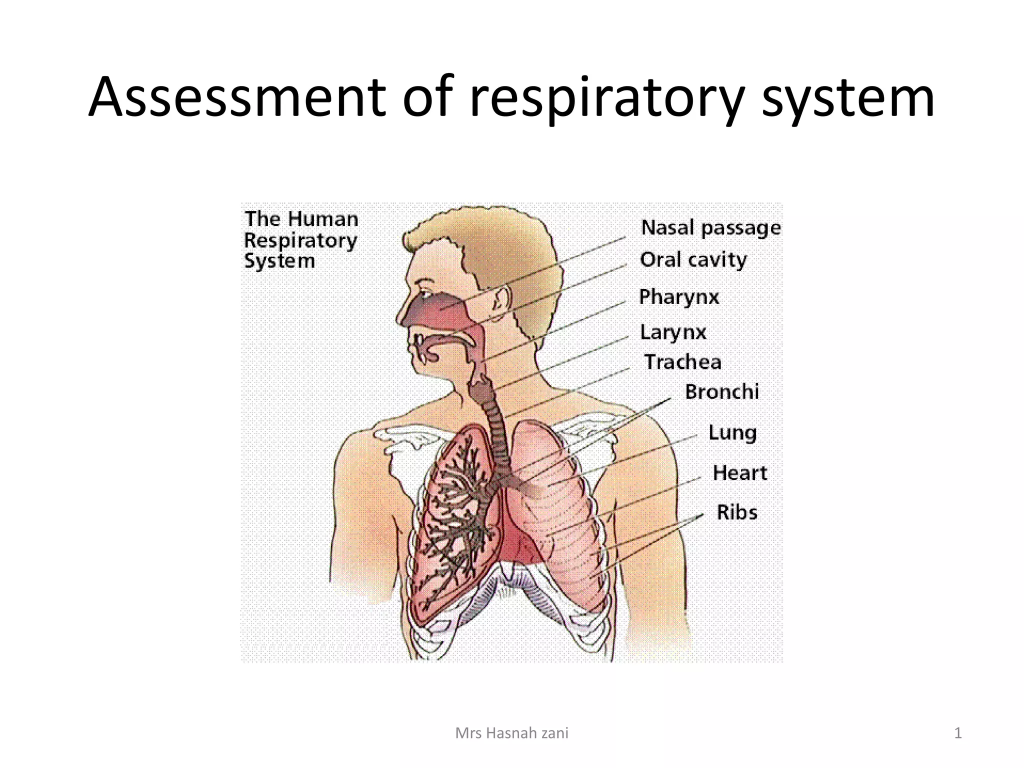

Assessment of respiratory function (અસેસમેન્ટ ઓફ રેસ્પીરેટ્રી ફંક્શન્સ):

Physical examination (ફિઝિકલ એક્ઝામિનેશન) / objective data (ઓબજેક્ટીવ ડેટા):

- રેસપાયરેટરી અસેસમેન્ટમાં મુખ્યત્વે હેડ, ચેસ્ટ, એક્સ્ટ્રીમિટીસ, ફિંગર અને ટોઝનો સમાવેશ થાય છે.